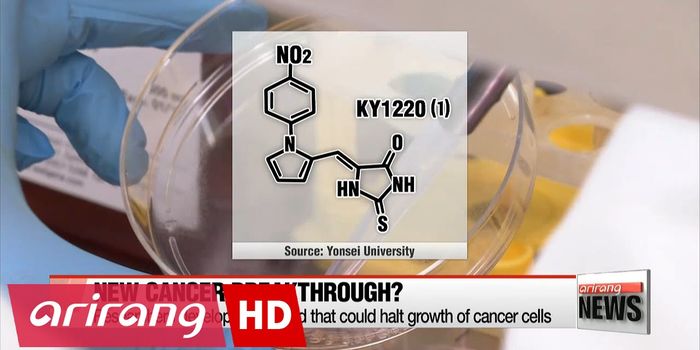

MAR 27, 2015VideosLast June, scientists at the University of Wisconsin Carbone Cancer Center (UWCCC) report that a new class of tumor-targ ...